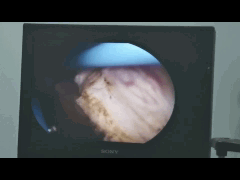

内镜下观察到增生非常严重的前列腺